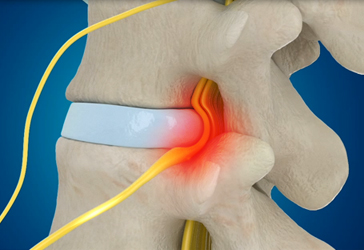

- 중증디스크 치료 기간 - 2개월 내

- 디스크가 터져서 통증을 일으키는 면적이 넓고 손상된 조직이 많기 때문에 일정 기간 이상의 치료시간이 필요합니다. 2개월 내 일상 생활 복귀를 목표로 치료합니다.